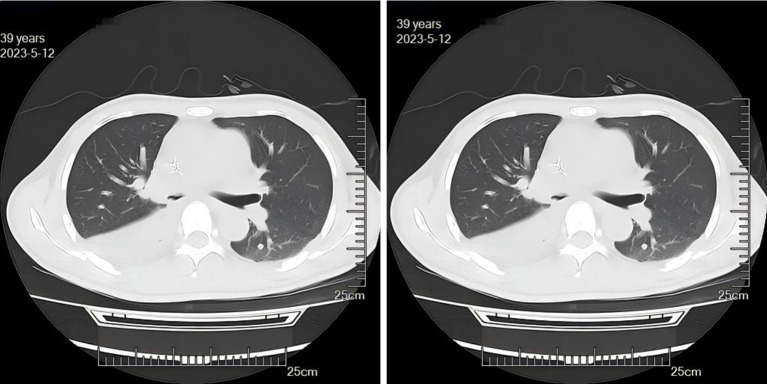

Case description: A 39-year-old male patient was diagnosed with PM and complicated by bronchial obstruction. Although surgical debridement of mucormycosis and antifungal therapy are generally preferred treatment, our patient presented with a high burden of invasive disease and was deemed ineligible for surgery. We therefore had to compromise and palliate his bronchial obstruction with a bronchial stent while continuing intravenous, nebulized, and bronchoscopically applied antifungals. The intervention markedly alleviated the patient's symptoms of chest tightness and dyspnea. However, given the advanced stage at presentation, the prognosis was already poor. Despite these measures, the aggressive underlying infection continued to progress, ultimately leading to erosion into a major vessel and catastrophic hemoptysis.

Conclusions: The implantation of bronchial stents in patients with PM can effectively alleviate severe bronchial obstruction caused by mucormycosis infection, improve pus drainage, and promote infection resolution. However, as a complete surgical resection of the lesion was not performed, the patient remains at risk of potentially catastrophic hemoptysis due to the possibility of pulmonary vascular invasion by mucormycosis. The potential increase in hemoptysis risk associated with stent implantation warrants further investigation.